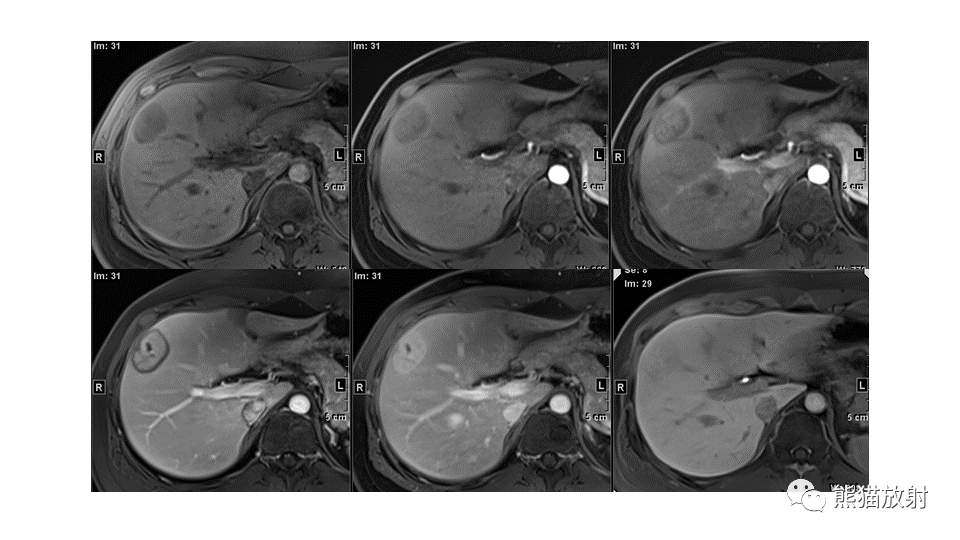

【PPT】肝内胆管细胞癌 VS 肝脓肿